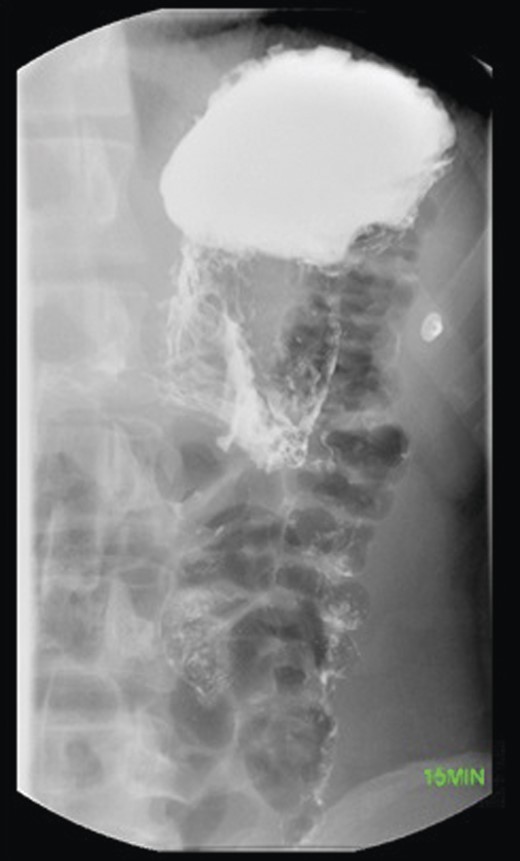

The laboratory results of the patient were creatinine 1.10 mg/dl (0.60–1.00), serum glucose 124 mg/dl (65–100), hemoglobin 16.9 µl (12.0–16.0) and total bilirubin 1.6 mg/dl (0.2–1.0). A gastroenterologist was consulted and an urgent EGD was done, showing negative insufflations of the stomach that were characteristic of a volvulus. The diagnosis of mesenteroaxial volvulus was confirmed by single contrast upper GI (UGI) imaging (Fig. 1).

The patient underwent a laparoscopic gastrostomy-tube gastropexy. A 10 mm laparoscope and three 5 mm ports were placed. There was no evidence of a hiatal hernia, diaphragmatic hernia or Meckel's diverticulum on visualization. The patient had healed well from his previous appendectomy. A crease on the stomach was visible where the volvulus had occurred. A 24-French gastrostomy tube was inserted percutaneously into the stomach and inflated. Using the gastrostomy tube, the stomach was approximated to the posterior aspect of the anterior abdominal wall. A point along the greater curve of the stomach, distal to the volvulus, was chosen to suture the stomach to the abdominal wall with permanent sutures. The patient tolerated the surgical procedure well (Fig. 2) and was discharged 4 days later.